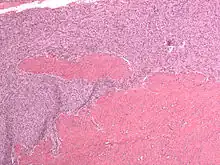

Micrograph of a low-grade endometrial stromal sarcoma. H&E stain.

Low-grade endometrial stromal sarcoma

Low-grade endometrial stromal sarcoma consists of cells resembling normal proliferative phase endometrium, but with infiltration or vascular invasion. These behave less[3] aggressively, sometimes metastasizing, with cancer stage the best predictor of survival. The cells express estrogen/progesterone-receptors.

• Monotonous ovoid cells to spindly cells with minimal cytoplasm.

• Prominent arterioles. Angiolymphatic invasion common.

• Up to 10-15 mitotic figures per 10 HPF in most active areas.

• Tongue-like infiltration between muscle bundles of myometrium.

• May exhibit myxoid, epithelioid and fibrous change.

• May have foam cells or hyalinization in the stroma.